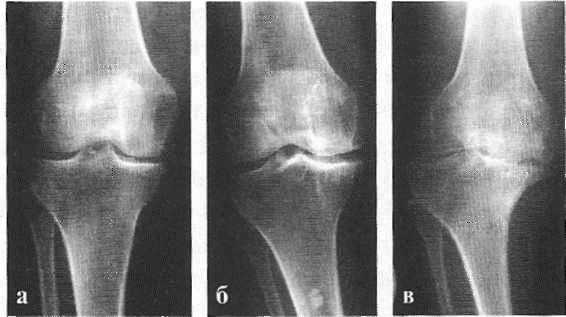

В подавляющем большинстве случаев достаточно осмотра и рентгенограммы коленного сустава в двух проекциях (прямой и боковой). [2] [19] Клинические данные и снимки позволяют определить стадию заболевания.

На ранних стадиях заболевания, при незначительных изменениях в костной ткани, рентгенологическое обследование не настолько ценно. [5] [8] На этом этапе гонартроз возможно диагностировать благодаря артроскопии. [5] [8] Точность метода очень высока, останавливать может только его инвазивный характер и цена.

В соответствии с клинико-рентгенологической картиной в развитии деформирующего остеоартроза выделяют 3 стадии:

- I - характеризуется незначительным уменьшением подвижности сустава, небольшим нечетким сужением суставной щели, начальными остеофитами на краях суставных плоскостей;

- II - протекает со снижением подвижности и хрустом в суставе при движении, умеренной мышечной атрофией, заметным сужением суставной щели, формированием значительных остеофитов и субхондрального остеосклероза в костной ткани;

- III - отличается деформацией сустава и резким ограничением его подвижности, отсутствием суставной щели, выраженной костной деформацией, наличием обширных остеофитов, субхондральных кист, суставных «мышей».